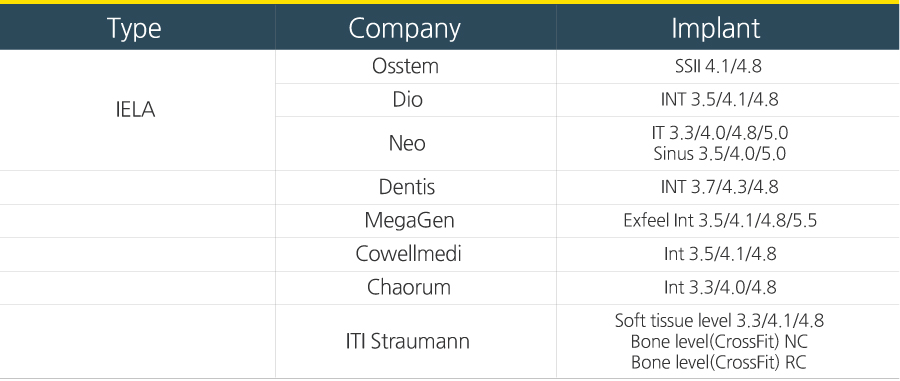

Compatible tableSubmerged

External

Internal

Bicon